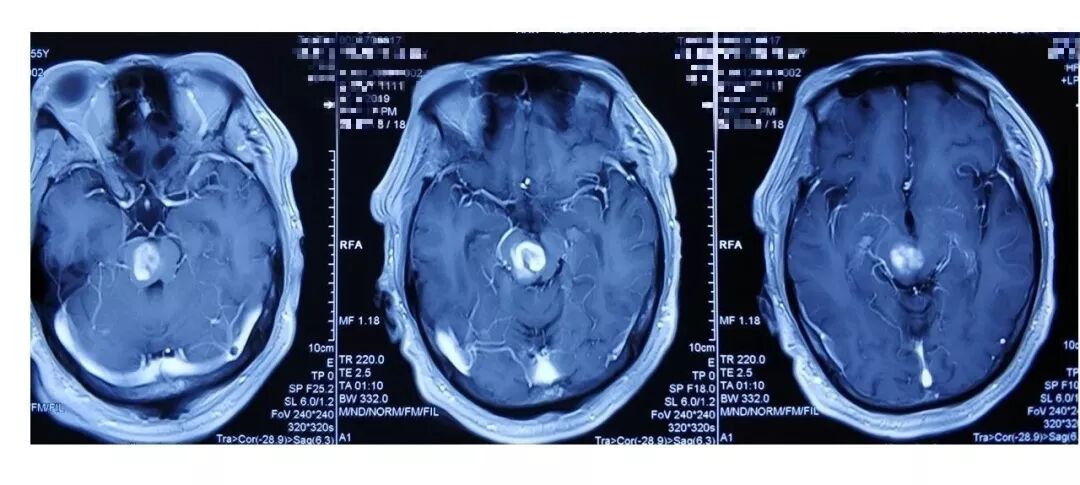

术前影像:透明隔腔明显增宽,双侧脑室、三脑室、脚间池明显扩张、积水,周围脑实质受压,胼胝体受压变薄。弥散加权图像未见异常。中线结构居中。增强扫描未见异常强化。

术前诊断:三脑室内囊肿,幕上脑积水。